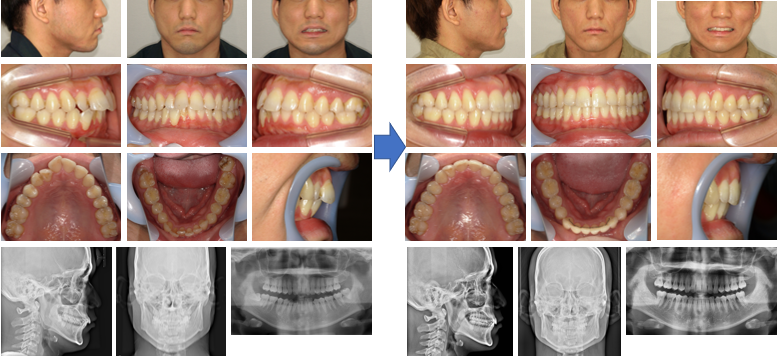

【治療例】初診時年齢:18歳8か月 / 性別:男性 / 主訴:上の歯のすきっ歯と出っ歯

本症例は、上顎前歯部の空隙と突出を気にして来院された。マウスピース型(アライナー型)矯正装置(インビザライン®)を用いて、上顎臼歯部の遠心移動とIPRを行いながら主訴の改善を図った。 その結果、上下前歯部間の距離は改善され、わずかであるが下顎の前方移動が認められた。

主訴:上の歯のすきっ歯と出っ歯

診断名:上顎前歯部にスぺースのある骨格性上顎前突症例

使用した主な装置:マウスピース型(アライナー型)矯正装置(インビザライン®)

抜歯/非抜歯および抜歯部位:非抜歯

※こちらの症例は2024年2月から2025年7月に行った矯正治療です(現在も経過観察中)

治療期間:1年5か月

治療回数:19回

リスクの副作用:歯の移動や抜歯による違和感や疼痛、口内炎、歯肉退縮、歯根吸収が生じることがある